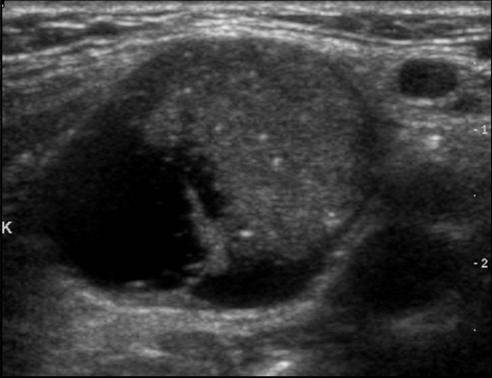

Ultraschall - echoarmer, unscharf begrenzter Knoten mit Krebsverdacht

Liegt ein kalter Knoten vor, so muss abgeklärt werden, ob es sich um einen "harmlosen" Knoten handelt oder ob Verdacht auf Schilddrüsenkrebs besteht. Neben der Szintigraphie ist heute primär der Ultraschall (Sonographie) die wichtigste Untersuchung zur Abklärung und Einschätzung von Knoten. "Echoreiche" und gut abgrenzbare Knoten deuten auf gutartigen Charakter hin harte, echoarme und schlecht abgrenzbare Adenome sind eher kritische Zeichen ebenso Knoten mit Mikrokalk, vor allem, wenn dasselbe Ultraschallmuster auch in Lymphknoten vorliegt. Metastasen in Lymphknoten zeigen häufig dasselbe Gewebebild.